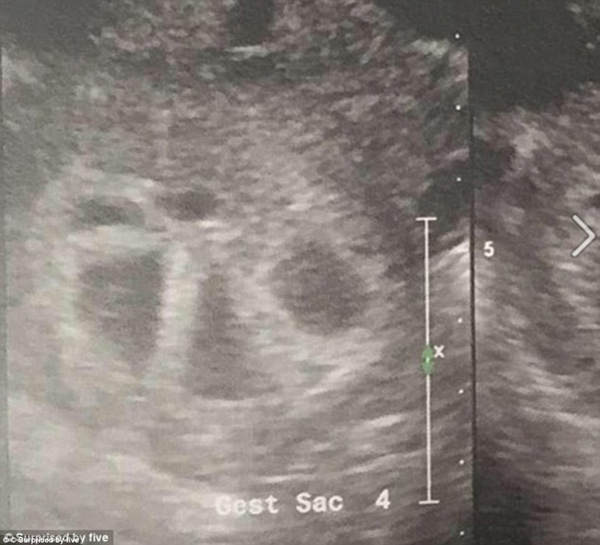

When she asked to use another sonogram machine so she could have a clearer view of the babies, her world was turned upside-down when the doctor found five separate heart beats.

Mrs Tucci asked to take a second sonogram to see her babies better and doctors were shocked to find out that instead of two heartbeats, there were five.

'My legs start [sic] to shake uncontrollably and all I can do is laugh.. The sonographer then told me the term for 5 is QUINTUPLETS!!' she continued.